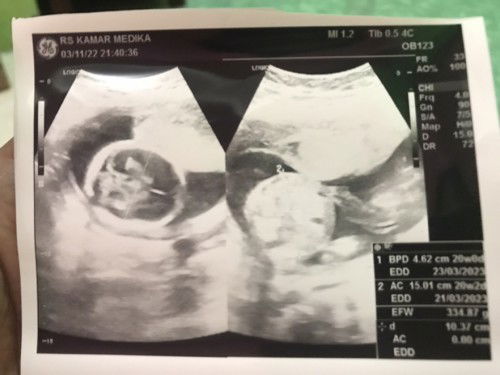

Hallo bunda, sharing dong yang uda pada usg dikehamilan 15 minggu bisa share foto usg dong.. penasaran bun kayak apa . Dan apakah diusia 15w sudah kelihatan JK nya ya bun ?? Saya jadwal usg masih diminggu 20 udah gak sabar bun . Kemarin usg di 12w belum kelihatan jk nya karna masih kecil.. Terimakasih #ingintahu